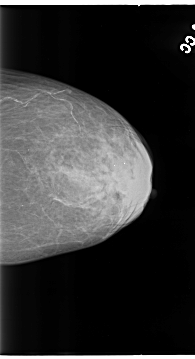

B_3130_1.LEFT_CC

LEFT_CC LINES 4664 PIXELS_PER_LINE 2528 BITS_PER_PIXEL 12 RESOLUTION 50 NON_OVERLAY

LEFT_MLO LINES 4624 PIXELS_PER_LINE 2664 BITS_PER_PIXEL 12 RESOLUTION 50 NON_OVERLAY